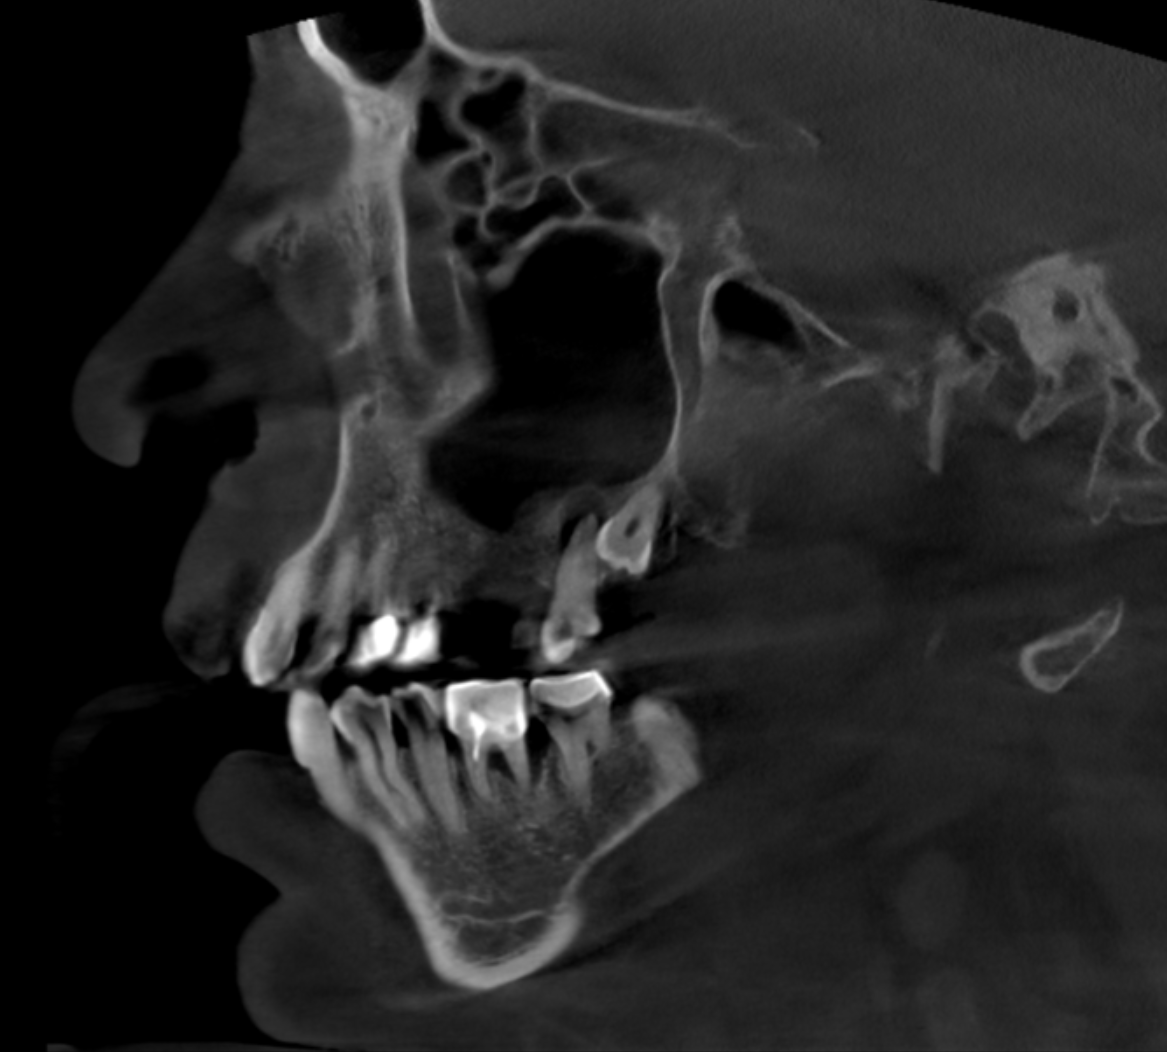

Fig. 4: Large-volume CBCT scan, sagittal cross-section of the right paranasal sinuses showing involvement of even the lower part of the cavernous sinus.

The extent of the inflammation was shocking (Figs. 2a & b). Not only the maxillary sinus (Fig. 3) but the ethmoid and sphenoid sinuses too were involved, and the inflammation had spread towards the right cavernous sinus as well (Fig. 4). At this point, extraction may have been the first choice for most dental clinicians, but we had to keep in mind that invasive treatment may have increased the risk of cavernous sinus thrombosis, a potentially avoidable possibility. There are very few circumstances under which a dental procedure can cause very severe or even lethal consequences, but this case approached such a situation.

As a first step, we informed the patient about our findings on the new CBCT scan and explained the severity of his dental condition and paranasal sinusitis (Figs. 5a-f). We immediately referred him to a hospital otolaryngology department for microbial examination and proper antibiotic treatment. After nine days of a high-dose amoxicillin and clavulanic acid therapy, the endodontic treatment could be started.